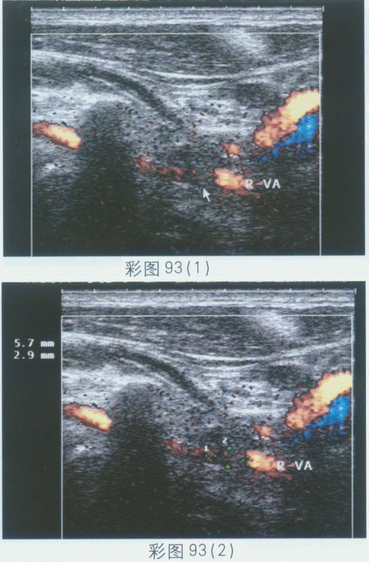

C.右椎动脉入椎前段

临床资料:男,50岁,头晕、头痛两年余。超声综合描述:左侧椎动脉内径0.43cm,右侧椎动脉内径0.30cm,距入椎前0.35cm处,管腔内透声不清亮,可探及0.4cm×0.27cm中等回声(箭头所指),该段残余管腔内径0.10cm,CDFI:该段血流明显变细,PW:入椎前V43.0cm/s,入椎后V55.0cm/s。见彩图93。

超声提示()。

A.右椎动脉入椎前斑块形成并狭窄

B.右椎动脉发育不全

C.右椎动脉走行变异

D.右椎动脉闭塞